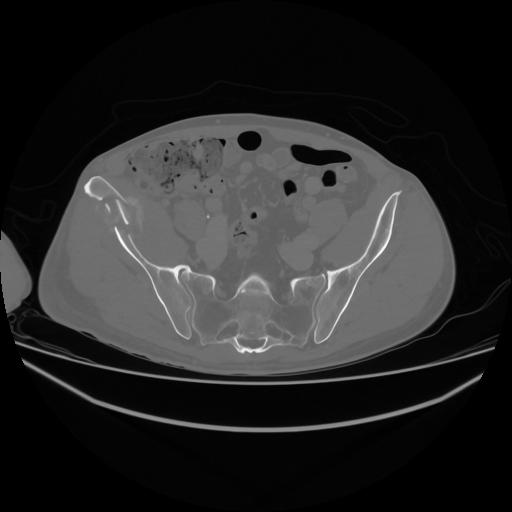

5 CUERPO,CE,Vol,1.0,CUERPO,,